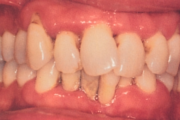

- igemed veritsevad (19)

- igemed punetavad (21)

- igemed on tursunud/vohavad (17)

- igemepiir on taandunud (3)